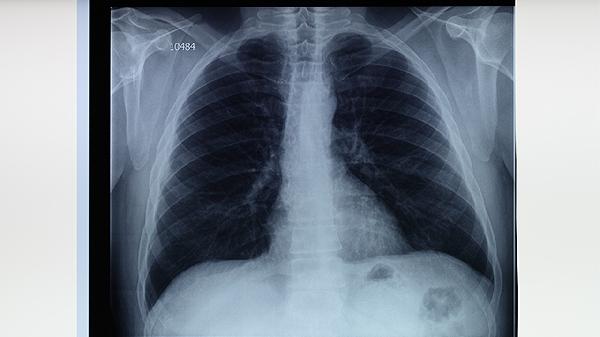

肺結(jié)核發(fā)作時除咳嗽、低熱等典型癥狀外,部分患者可能出現(xiàn)關(guān)節(jié)疼痛、皮膚結(jié)節(jié)、月經(jīng)紊亂等不常見表現(xiàn)。肺結(jié)核是由結(jié)核分枝桿菌感染引起的慢性傳染病,主要累及肺部,但也可侵犯其他器官。